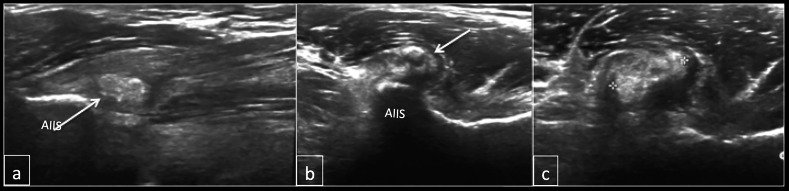

Fig. 2.

Longitudinal (a) and axial (b and c) of the hip demonstrating amorphous calcification within the direct head of rectus femoris (arrow). AIIS- anterior inferior iliac spine